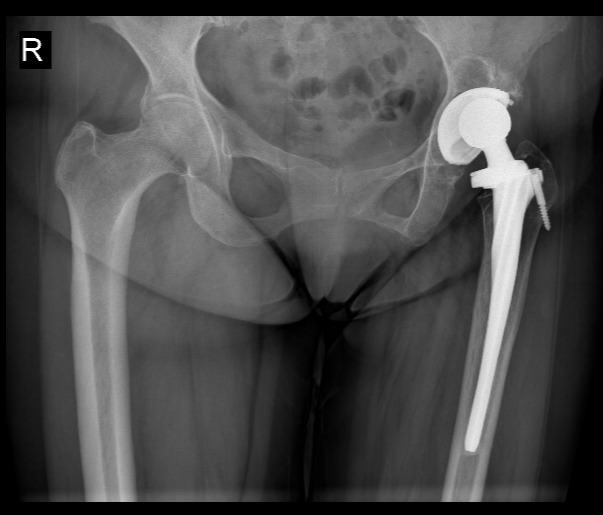

针对该病例,北京积水潭医院郑州医院(郑州市中心医院)副院长杨德金带领团队通过多学科会诊制定个性化方案:

一方面协调适配的翻修假体材料,完善术前备血等准备

另一方面在术中采用垫块重建髋臼结构,并通过周围肌肉与补片编织技术修复臀中肌功能,最终完成手术。